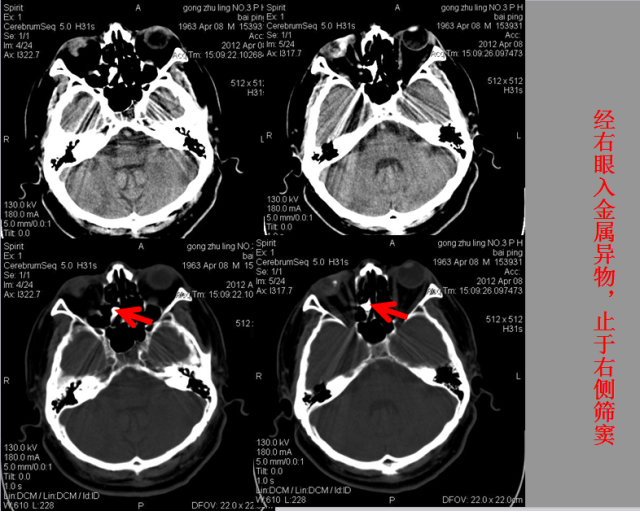

急性颅脑损伤篇

急胸症篇